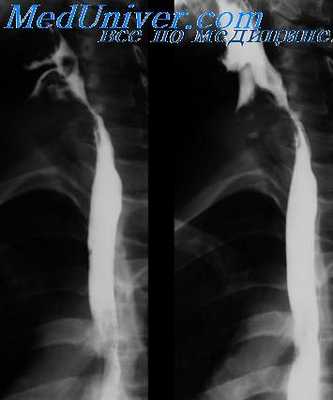

Относительно рентгенологического исследования пищевода следует сказать, что этот метод позволяет в ряде случаев, во-первых, исключить опухоли, исходящие из пищевода; во-вторых, более точно определить локализацию патологического образования в средостении и, в-третьих, установить отношение пищевода к медиастинальному процессу.

Послойное исследование при заполненном водной взвесью бария или воздухом пищевода (И. Т. Шевченко), а тем более еще и при введении воздуха в средостение (И. А. Шехтер, Е. С. Лушников и Б. Я- Лукьянченко) расширяет диагностические возможности при заболеваниях средостения.